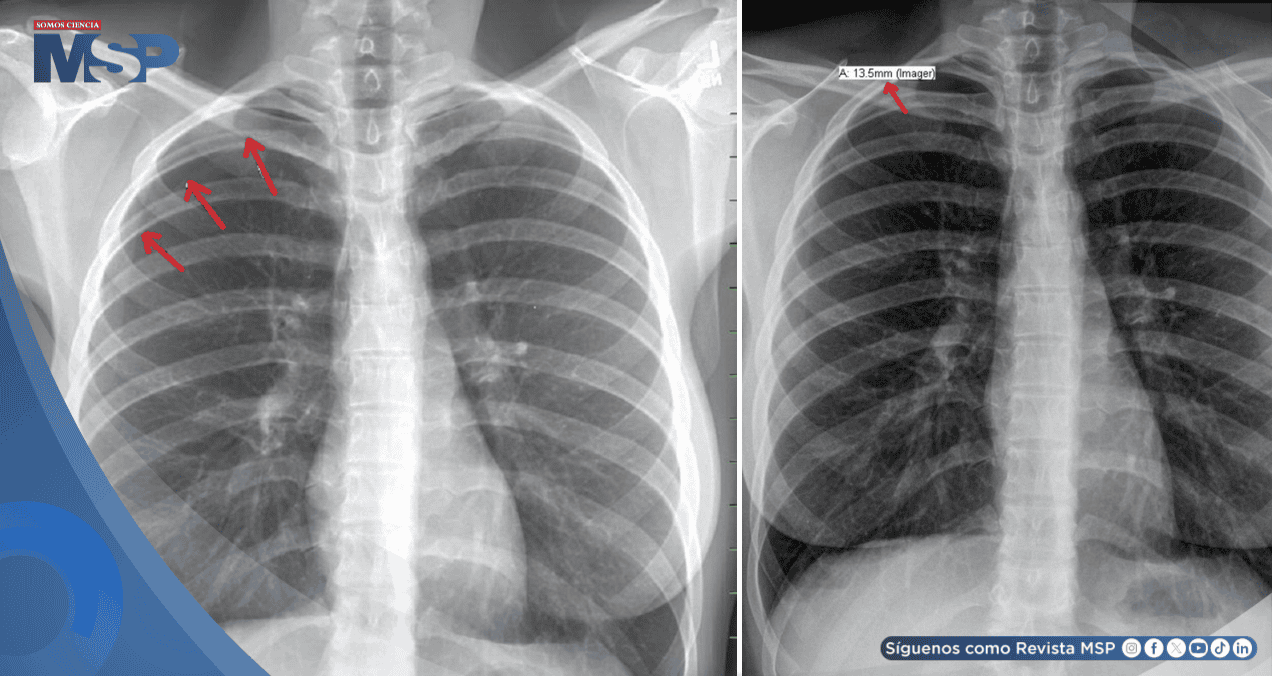

No obstante, la auscultación reveló una disminución del murmullo vesicular en el hemitórax derecho. Una radiografía de tórax confirmó el diagnóstico: un neumotórax derecho iatrogénico, con un colapso pulmonar del 20%, atribuido directamente a la punción seca.